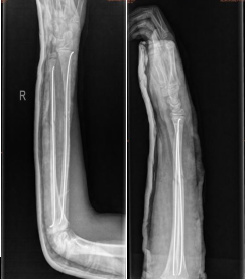

我科典型病例:

5岁男童,尺桡骨双骨折

术前